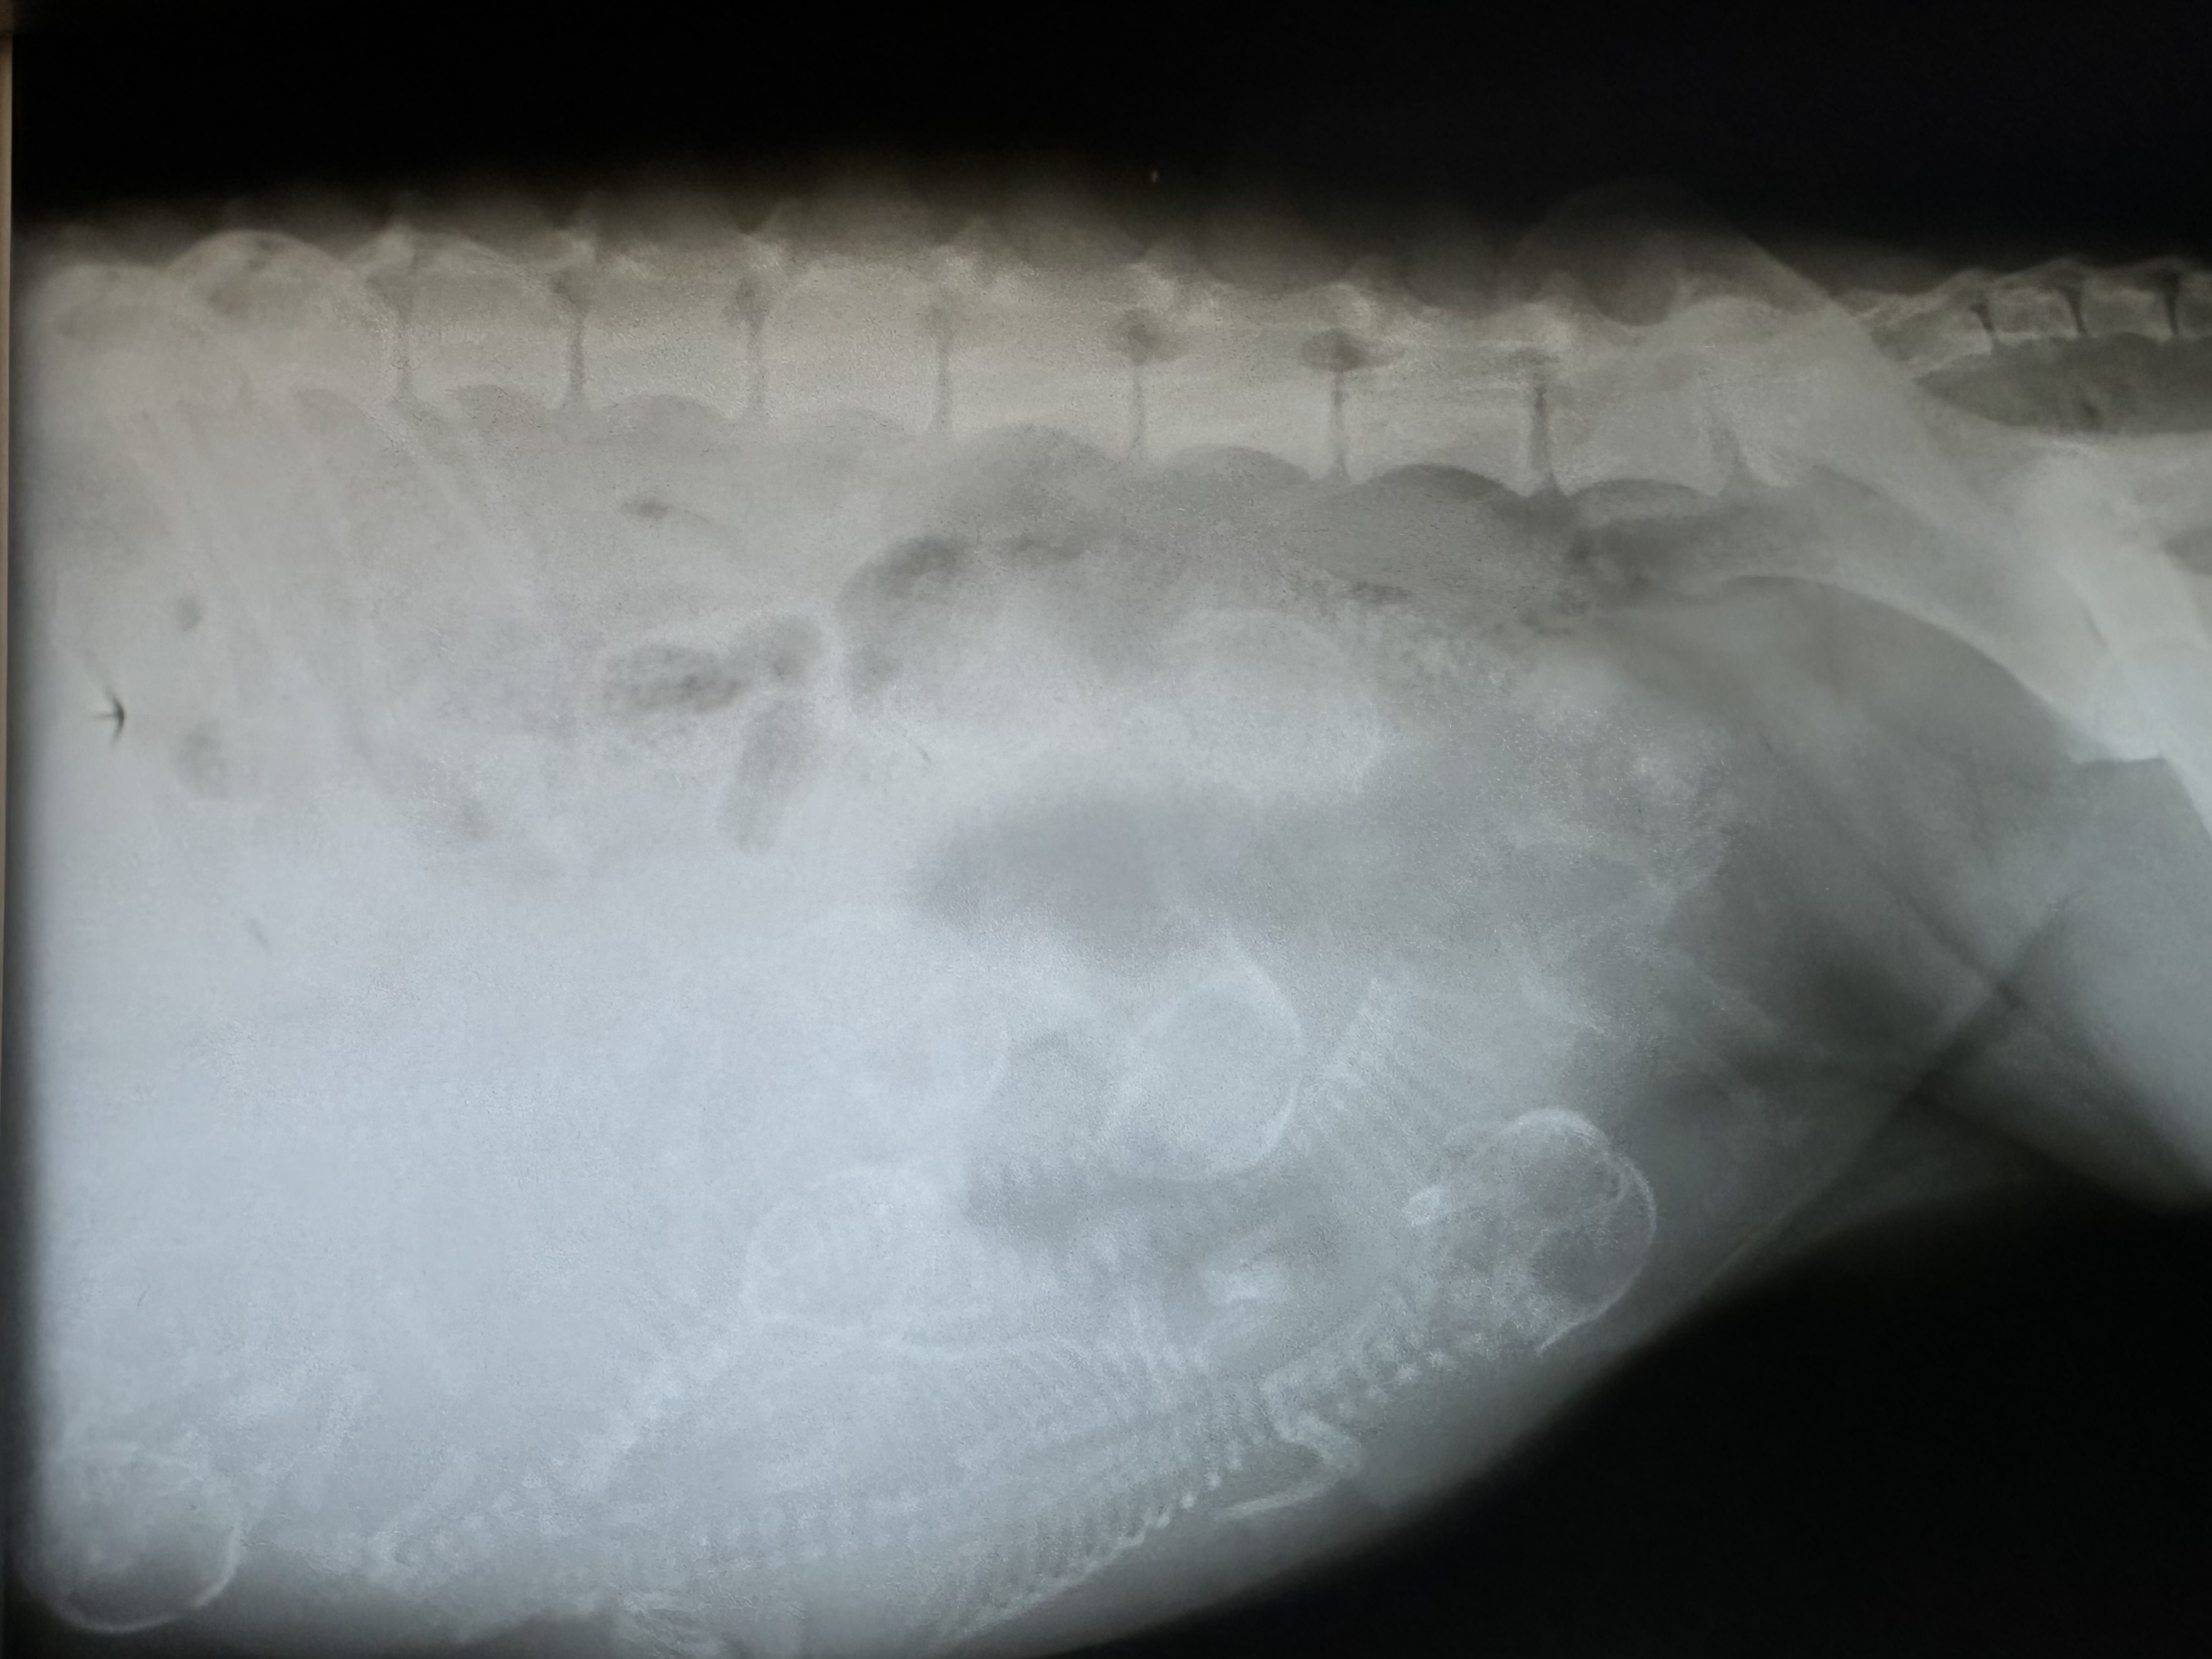

Heute ist bereits Tag 57 der Trächtigkeit. Masha hat knapp 5 Kg zugenommen und ein stattliches Bäuchlein bekommen. Von oben kaum zu sehen, ist es von der Seite unübersehbar. Die letzten Tage war sie dauerhungrig, was sich nun nach dem heutigen Röntgentermin auch erklärt.

2024 10 18 C1 Wurf Tag57 IMG 4101

Somit hoffen wir in den kommenden Tagen auf eine komplikationslose Geburt.

Ein wenig Geduld brauchen wir nun noch :-)